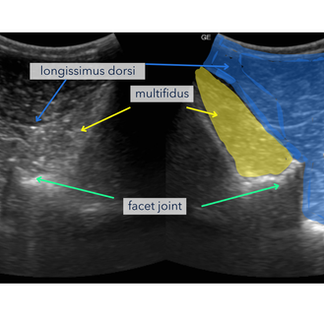

Degenerative changes affecting the synovial intervertebral (facet) joints can be frequently seen in the caudal thoracic and lumbar regions.

This area can often be overlooked due to the more technical ultrasonography skils orequired to assess this region. This area is unable to be seen on regular field x-rays due to the tissue thickness.

The longissimus dorsi and multifidus are essential for stabilising and supporting the spine. Injury or chronic overload leads to reactive tension, loss of symmetry, or postural compromise. Diganosis is via ultrasonographic assessment, muscle scoring and palpation.

Ultrasound:

Ultrasound is very useful to penetrate to deeper tissues of the horse's back. We use it to identify bone changes at the level of the joints (arthritis) and for a assessing soft tissues (ligaments & muscle).

Ultrasound guided treatments ensure that specific structures are targeted to have the greatest effect possible.